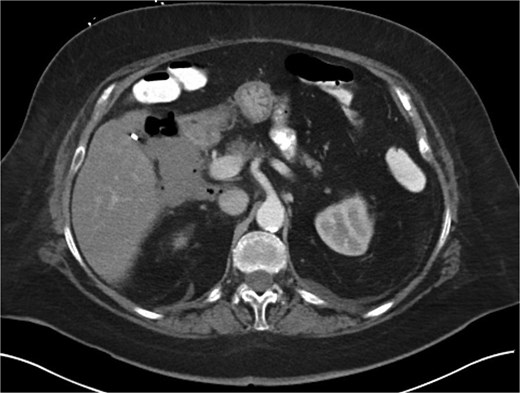

A 70-year-old woman with obesity, non-insulin-dependent diabetes, gastroesophageal reflux disease (GERD), cholecystectomy, and prior RYGB presented to the ED with acute chest and lower abdominal pain. The pain began 1 day earlier and initially responded to Ibuprofen, which she had been taking 4–6 times daily for musculoskeletal discomfort. Her pain worsened, radiating to her back, and was accompanied by belching and vomiting with dry heaving. She denied trauma or changes in bowel habits. Initial CT (Fig. 1) imaging showed a moderate hyperdense area around the duodenum, distension of the afferent limb and excluded stomach, and expected postoperative changes. She was admitted for conservative management. Four days later, a repeat CT (Fig. 2) was performed due to persistent symptoms, revealing free fluid in the intraperitoneal and retroperitoneal spaces, raising concern for duodenal perforation. She developed lethargy and diffuse abdominal tenderness and was taken to the operating room. Exploratory laparotomy with peritoneal washout, enterolysis, partial omentectomy was performed. It revealed two 1 cm posterolateral perforations of D3, which were repaired with an omental pedicle flap. The Roux limb was healthy, the jejunojejunostomy was dilated but patent, and the biliopancreatic limb was intact. Due to high vasopressor requirements, a temporary abdominal closure device was placed, and she was transferred to the surgical ICU. After stabilization, a second-look laparotomy was performed the next day to reinforce the duodenal closure, place a gastrostomy tube for drainage, and insert a J-tube for feeding (Figs 3 and 4). The abdominal wall was closed. On postoperative day 2, a CT with contrast showed extravasation from the duodenal repair site. Interventional radiology placed a transhepatic biliary drain to divert bile and support duodenal patch healing. Helicobacter pylori antigen was negative. Her condition improved, and she was started on an enteral and slow oral feeding regimen. However, at this juncture, the patient declined further treatment and requested comfort care measures.

Intra-operative image showing pyloroplasty and omental patch repair.